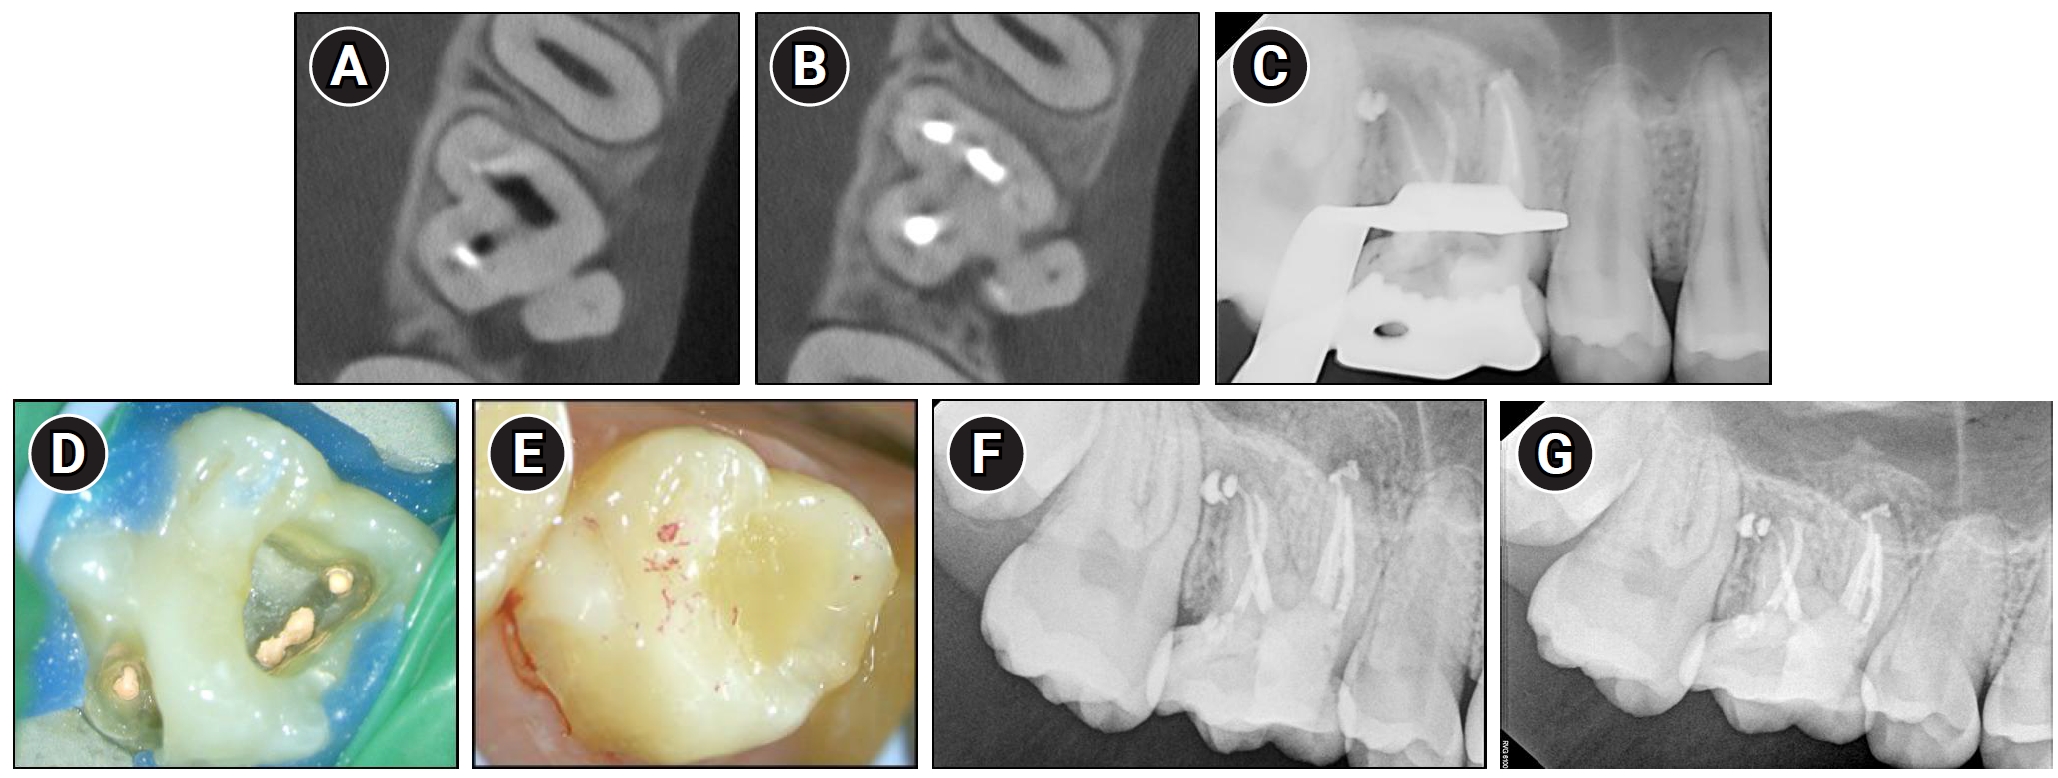

Identification and treatment of the palatal canal through buccal access in maxillary right first molar (#16). (A, B) Re-taken Cone-beam computed tomography axial views showing the palatal canal located more mesially than initially anticipated. (C) Radiograph taken after obturation of the palatal canal. (D) Clinical view of the completed obturation including the palatal canal. (E) Clinical view of the core buildup, demonstrating proper occlusal contacts. (F) One-month follow-up radiographs demonstrating reduction of the periapical radiolucency. (G) Five-month follow-up radiographs showing a further reduction of the periapical radiolucency.

At the third visit, to find the palatal canal, a second CBCT scan was obtained. The canal was found to be located in a more mesio-palatal position than initially anticipated (Figure 3A and B). Working length determination, canal instrumentation, and irrigation were subsequently performed using the same protocol and instruments as those employed for the buccal canals.

At the following visit, obturation of the palatal canal was performed using the same technique and materials as used for the buccal canals using a sealer-based technique. Core buildup was then completed using bonding (Scotchbond Universal Adhesive; 3M ESPE, St. Paul, MN, USA) and resin core (Filtek Fill and Core, 3M ESPE) (Figure 3C–E).

Serial follow-up evaluations revealed progressive healing, as the periapical lesion showed a gradual reduction in size—initially evident at 1 month (Figure 3F) and continuing to further resolution by 5 months (Figure 3G). The patient is scheduled for continued follow-up evaluations.

In the present case, both a CMD and an open channel were identified, consistent with previously reported anatomical features of MIM (Figure 4A–C). A periapical lesion developed despite the absence of caries or visible fractures, which are typically associated with pulpal infection. This unusual clinical finding may be explained by the presence of structural anomalies commonly seen in MIM, specifically microporosities within the CMD and an open furcal channel. The CMD-associated microporosities could have acted as microchannels for bacterial ingress, promoting chronic intrapulpal infection. Additionally, the open channel observed in the furcation area may have established a direct connection between the oral environment and the pulp chamber, serving as a potential route for bacterial contamination. Together, these features likely contributed to pulpal pathology and the development of the periapical lesion in the absence of conventional etiological factors.

Cone-beam computed tomography images revealing characteristic anatomical features of molar-incisor malformation. (A, B) A dense mineralized structure consistent with a cervical mineralized diaphragm (yellow arrows). (C) An open channel (yellow arrow) connecting the furcation region to the pulp chamber.